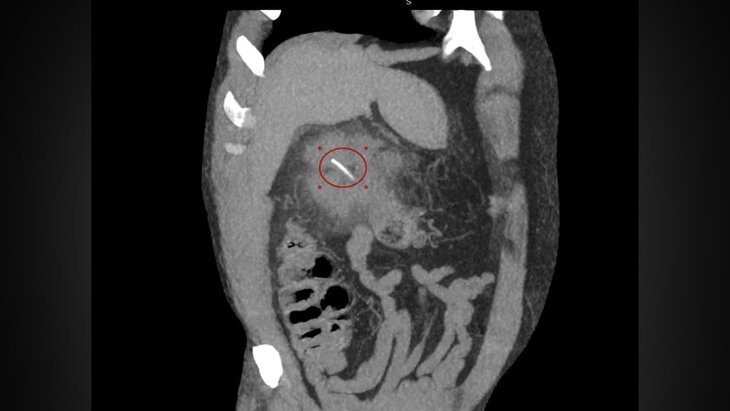

Подмосковные врачи спасли мужчину, которому рыбья кость проткнула кишечник